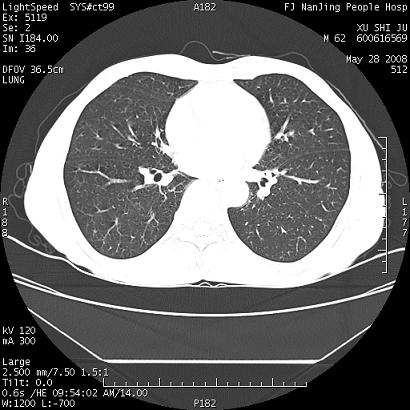

以下是引用杀毒软件在2008-5-28 19:16:00的发言:[br]病灶旁“晕轮征”,考虑肺真菌病

以下是引用qiushi在2008-5-28 20:01:00的发言:[br]空洞周围环状磨玻璃影(日晕征),考虑肺曲霉菌病.

以下是引用yuhongjun在2008-5-29 4:28:00的发言:[br]空洞周围环状磨玻璃影(日晕征),考虑肺曲霉菌病。支持! [br] [br]

以下是引用lrj在2008-5-28 21:10:00的发言:[br]所示应该是正常结构,是对称的,多个层面都有!也不像是内乳动脉或是肿大淋巴结![br]右下肺渗出性病变伴空洞形成,其洞内见一结节,以下诊断都有可能:1 右下肺曲菌感染, 2右下肺结核空洞形成伴曲菌感染!3右下肺结核空洞伴壁内占位形成,虽说后者发生的几率很低 但作为我们应该多考虑一下吧!最重要的结合临床